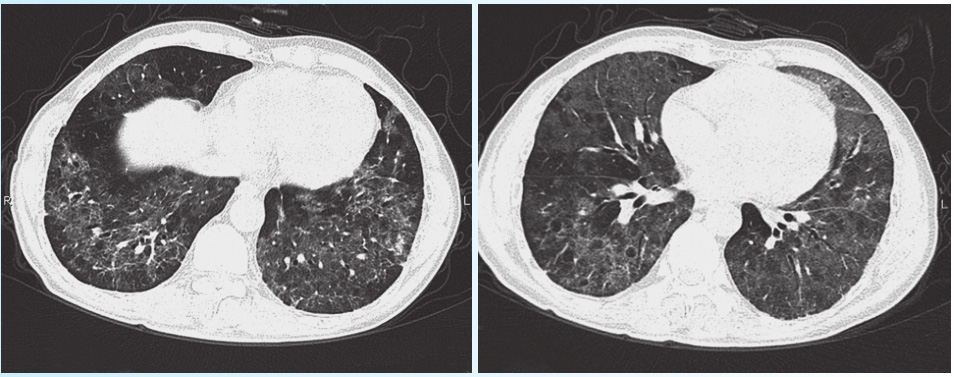

患者,男性,35岁,因“发热伴呼吸困难2个月”来门诊就诊。患者2013年12月初无诱因出现发热,最高体温39.0℃,伴胸闷及憋气,偶有咳黏痰,同时伴有头痛、膝关节及腰部疼痛,无其他不适,就诊于当地医院,查血常规:WBC 12.33×10 9 /L,中性粒细胞百分比82.7%,Hb 149g/L,PLT 162×10 9 /L。肝肾功能、尿常规均(−)。肺CT示双肺弥漫性病变(图2-2-1)。考虑肺部感染,予抗炎治疗(不详),无好转。既往体健。查体:呼吸急促,呼吸30次/min,SpO 2 90%,双肺呼吸音粗,未闻及干湿啰音,心腹查体(−)。

图2-2-1 肺部CT图像

该患者存在发热、胸闷、憋气、咳嗽,白细胞及中性粒细胞增多,胸部CT示双肺病变,考虑肺部感染诊断明确。患者发病地点在社区,而非医疗机构,所以考虑社区获得性肺炎。